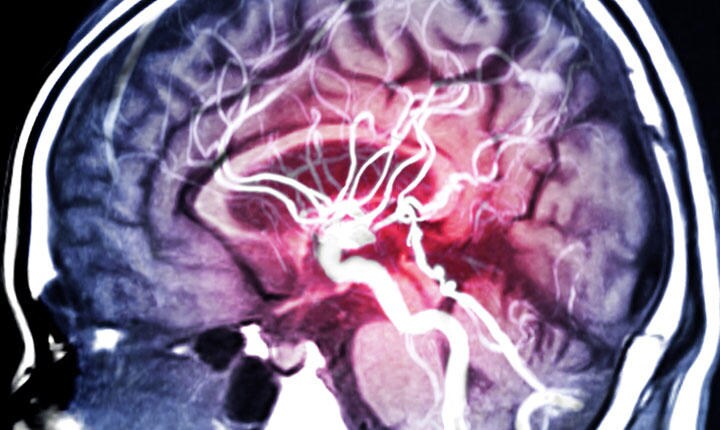

耳につけるだけで心が落ち着くイヤホンから、額につけるだけでストレスを軽減できる小型デバイスまで、神経組織を刺激し、その活動に干渉するニューロモジュレーションの領域が、ここにきて急速に進化している。

ニューロモジュレーションには、経頭蓋直流刺激(tDCS)、経頭蓋磁気刺激(TMS)、迷走神経刺激(VNS)など、いろいろなタイプがある。直流電流、交流電流、磁気、近赤外線、超音波など、与える刺激はいろいろあるが、どの刺激でも医療用としては、鬱やてんかん、痛み緩和などに用いられることが多い。一方、消費者向けのデバイスとしては体内に埋め込む必要のないウエアラブル機器としての開発、市販化が進んでいる。消費者向けデバイスは、リラックス効果や、認知能力や、記憶力、スポーツのパフォーマンスの向上などをうたっているものが多いようだ。